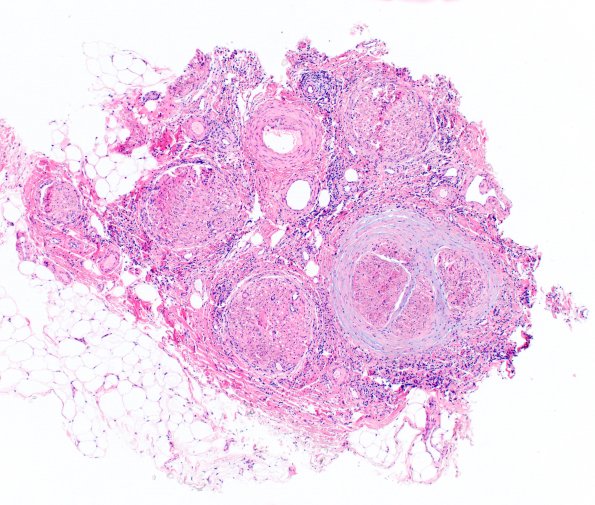

Case 1 History ---- The patient is a 50-year-old man with a history of metastatic melanoma status post combined ipilimumab and nivolumab adjuvant therapy who presented with progressive proximal greater than distal lower extremity weakness for 1 month, leading to admission in 11/2020. EMG revealed axonal sensory motor neuropathy. A paraneoplastic panel was negative. Operative procedure: Right sural nerve and gastrocnemius muscle biopsies. Electrodiagnostic testing showed an axonal polyneuropathy. ---- 1A1 This low magnification image shows uneven distribution of inflammation, perineurial fibrosis and some myxoid change within the perineurial sheath. (H&E)